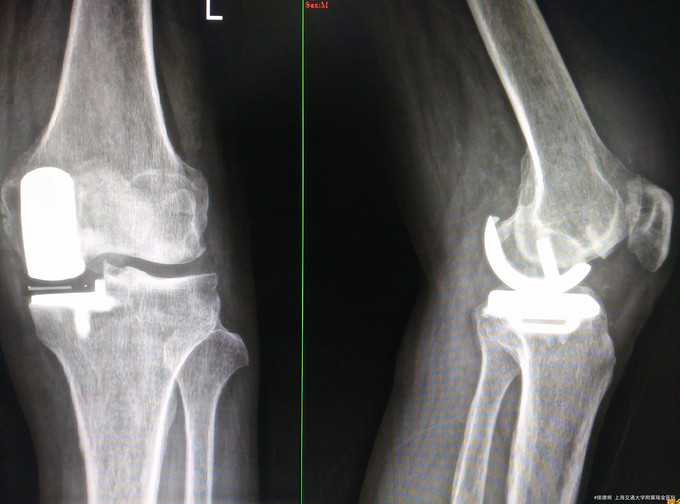

诊断: 左侧膝关节退行性病变 处理:左侧膝关节单髁置换术

随访: 术后1周膝关节屈伸活动好,术后2周手术切口愈合好。 讨论: 对于单髁置换术后的患者,请讨论抗凝的方法和抗凝时间。术后是否使用关节松动训练?